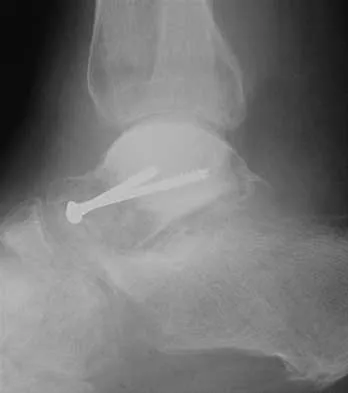

A 45-year-old man who underwent an ankle arthrodesis reports that for the first 6 years he had significant pain relief after the fusion healed. However, he now has increasing pain in the sinus tarsi. AP and lateral radiographs are shown in Figures 8a and 8b. What is the most likely cause of the patient's symptoms?

The patient has a solid ankle fusion radiographically. With a tibiotalar arthrodesis, the adjacent joints (subtalar and transverse tarsal) take additional stress. Over time, progressive degenerative arthritis will occur in these adjacent joints, often necessitating further surgery. Beaty JH (ed): Orthopaedic Knowledge Update 6. Rosemont, IL, American Academy of Orthopaedic Surgeons, 1999, pp 613-631.